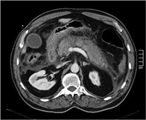

Presentation of secondary parasitic infection 37 years after primary infection

Gary Sharp and others

Journal of Surgical Case Reports, Volume 2017, Issue 6, June 2017, rjx103, https://doi.org/10.1093/jscr/rjx103